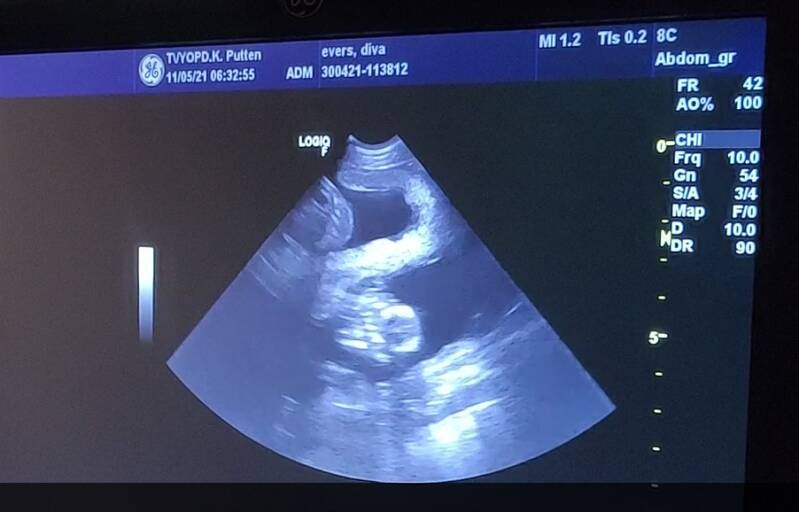

Omdat de echo bij Diva geen duidelijk beeld gaf van levende embryo's besloot ik om 10 dagen later nog een echo te laten maken. Hopelijk konden we dan wel teken van leven vinden en zou ik iets meer duidelijkheid krijgen of het er inderdaad maar een of twee zouden zijn.

Maar tot onze verbazing zagen we al snel 3 hele duidelijke hartjes en twijfelde de dierenarts of er niet toch nog meer 'verstopt' zat. Een 4e of 5e pup wilde ze dus nog niet uitsluiten. Een groot nest wordt het sowieso niet, maar het feit dat er sowieso 3 hartjes gezien zijn, vergroot de kans op een natuurlijke bevalling enorm! Laten we duimen dat nu alles goed gaat en er straks 3 of 4 gezonde pups geboren mogen worden!?